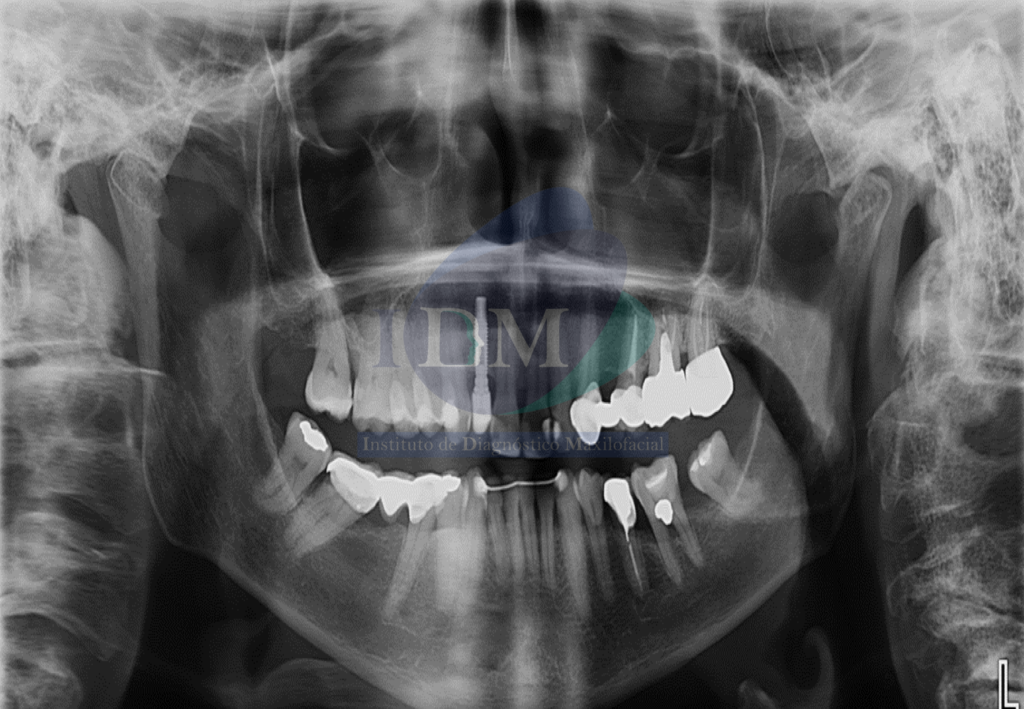

En la radiografía panorámica se observan signos de aplanamiento del contorno de los cóndilos mandibulares y esclerosis del cóndilo mandibular izquierdo.

Radiografia Panorámica